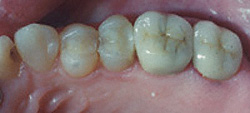

Before

After

Mark Pelletier, D.D.S. in Irmo has a few questions for you. Do you have a cracked or broken tooth? What about a tooth that's decayed too much to hold a filling? Did you know that if the crack or decay extends into your root, you will have an even worse problem on your hand? Dental crowns are a natural-looking and comfortable solution to cracked, broken, or excessively decayed teeth.

A crown is a metal or porcelain cap that covers the problematic tooth completely. Dr. Pelletier can fit crowns tightly at the base of a patient's gum and in order to protect what remains of the natural tooth.